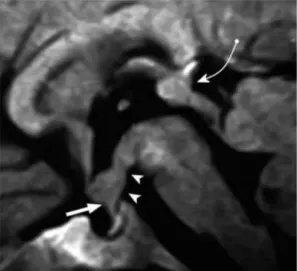

图:3岁女童,中枢性尿崩症。矢状位增强T1加权磁共振成像显示一个清晰的、分叶的、均匀增强的肿块(生殖细胞瘤),累及垂体柄近端(直箭头)和下丘脑底部(箭头)。还可见松果体相关的生殖细胞瘤(弯箭头)。术后诊断下丘脑和松果体异体生殖细胞瘤

MRI:T1等信号,无增强;T2等信号或稍高信号。